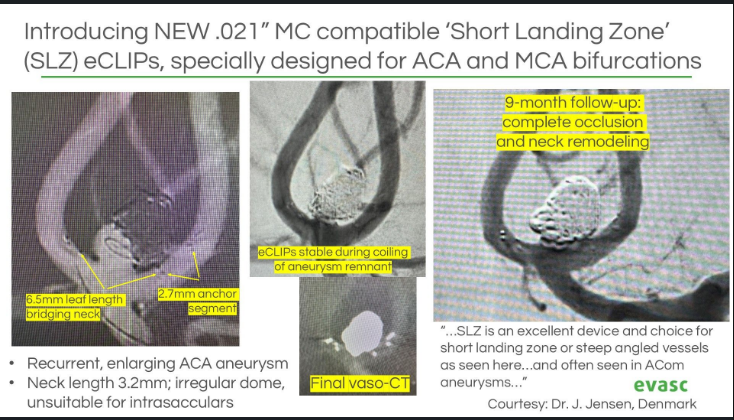

Real-world data confirm #eCLIPs delivers durable, efficient & safe outcomes for #WNBAs — now published in Neurosurgery Publications . Plus: CE/MDR approval & limited launch of our 0.021" compatible eBFD. 📄 Study: bit.ly/4lezYWp 🔗 PR: bit.ly/41oko3f #Neurointervention